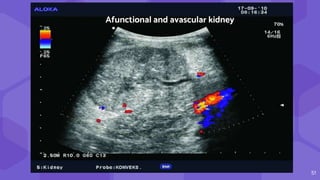

● Hyperacute

rejection

● No signs of blood

flow

Afunctional and avascular kidney